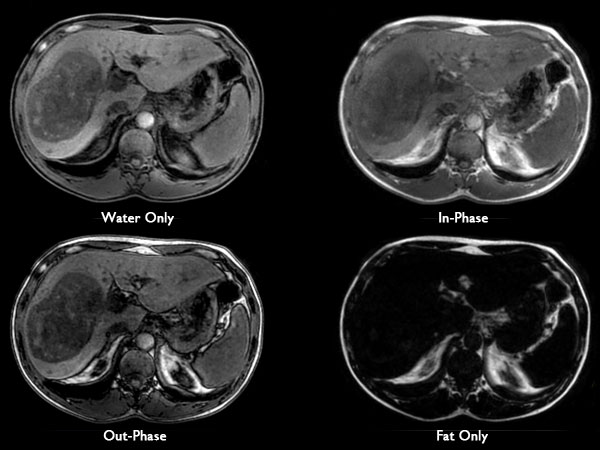

62 year old patient with huge, non-cirrhotic liver tumor. Question is if the portal vein is closed or not which has a direct influence on treatment options. Portal vein turned out to be open and patient was referred for embolization. No other tumors / lesions were found.

Axial mDIXON (pre-gado)